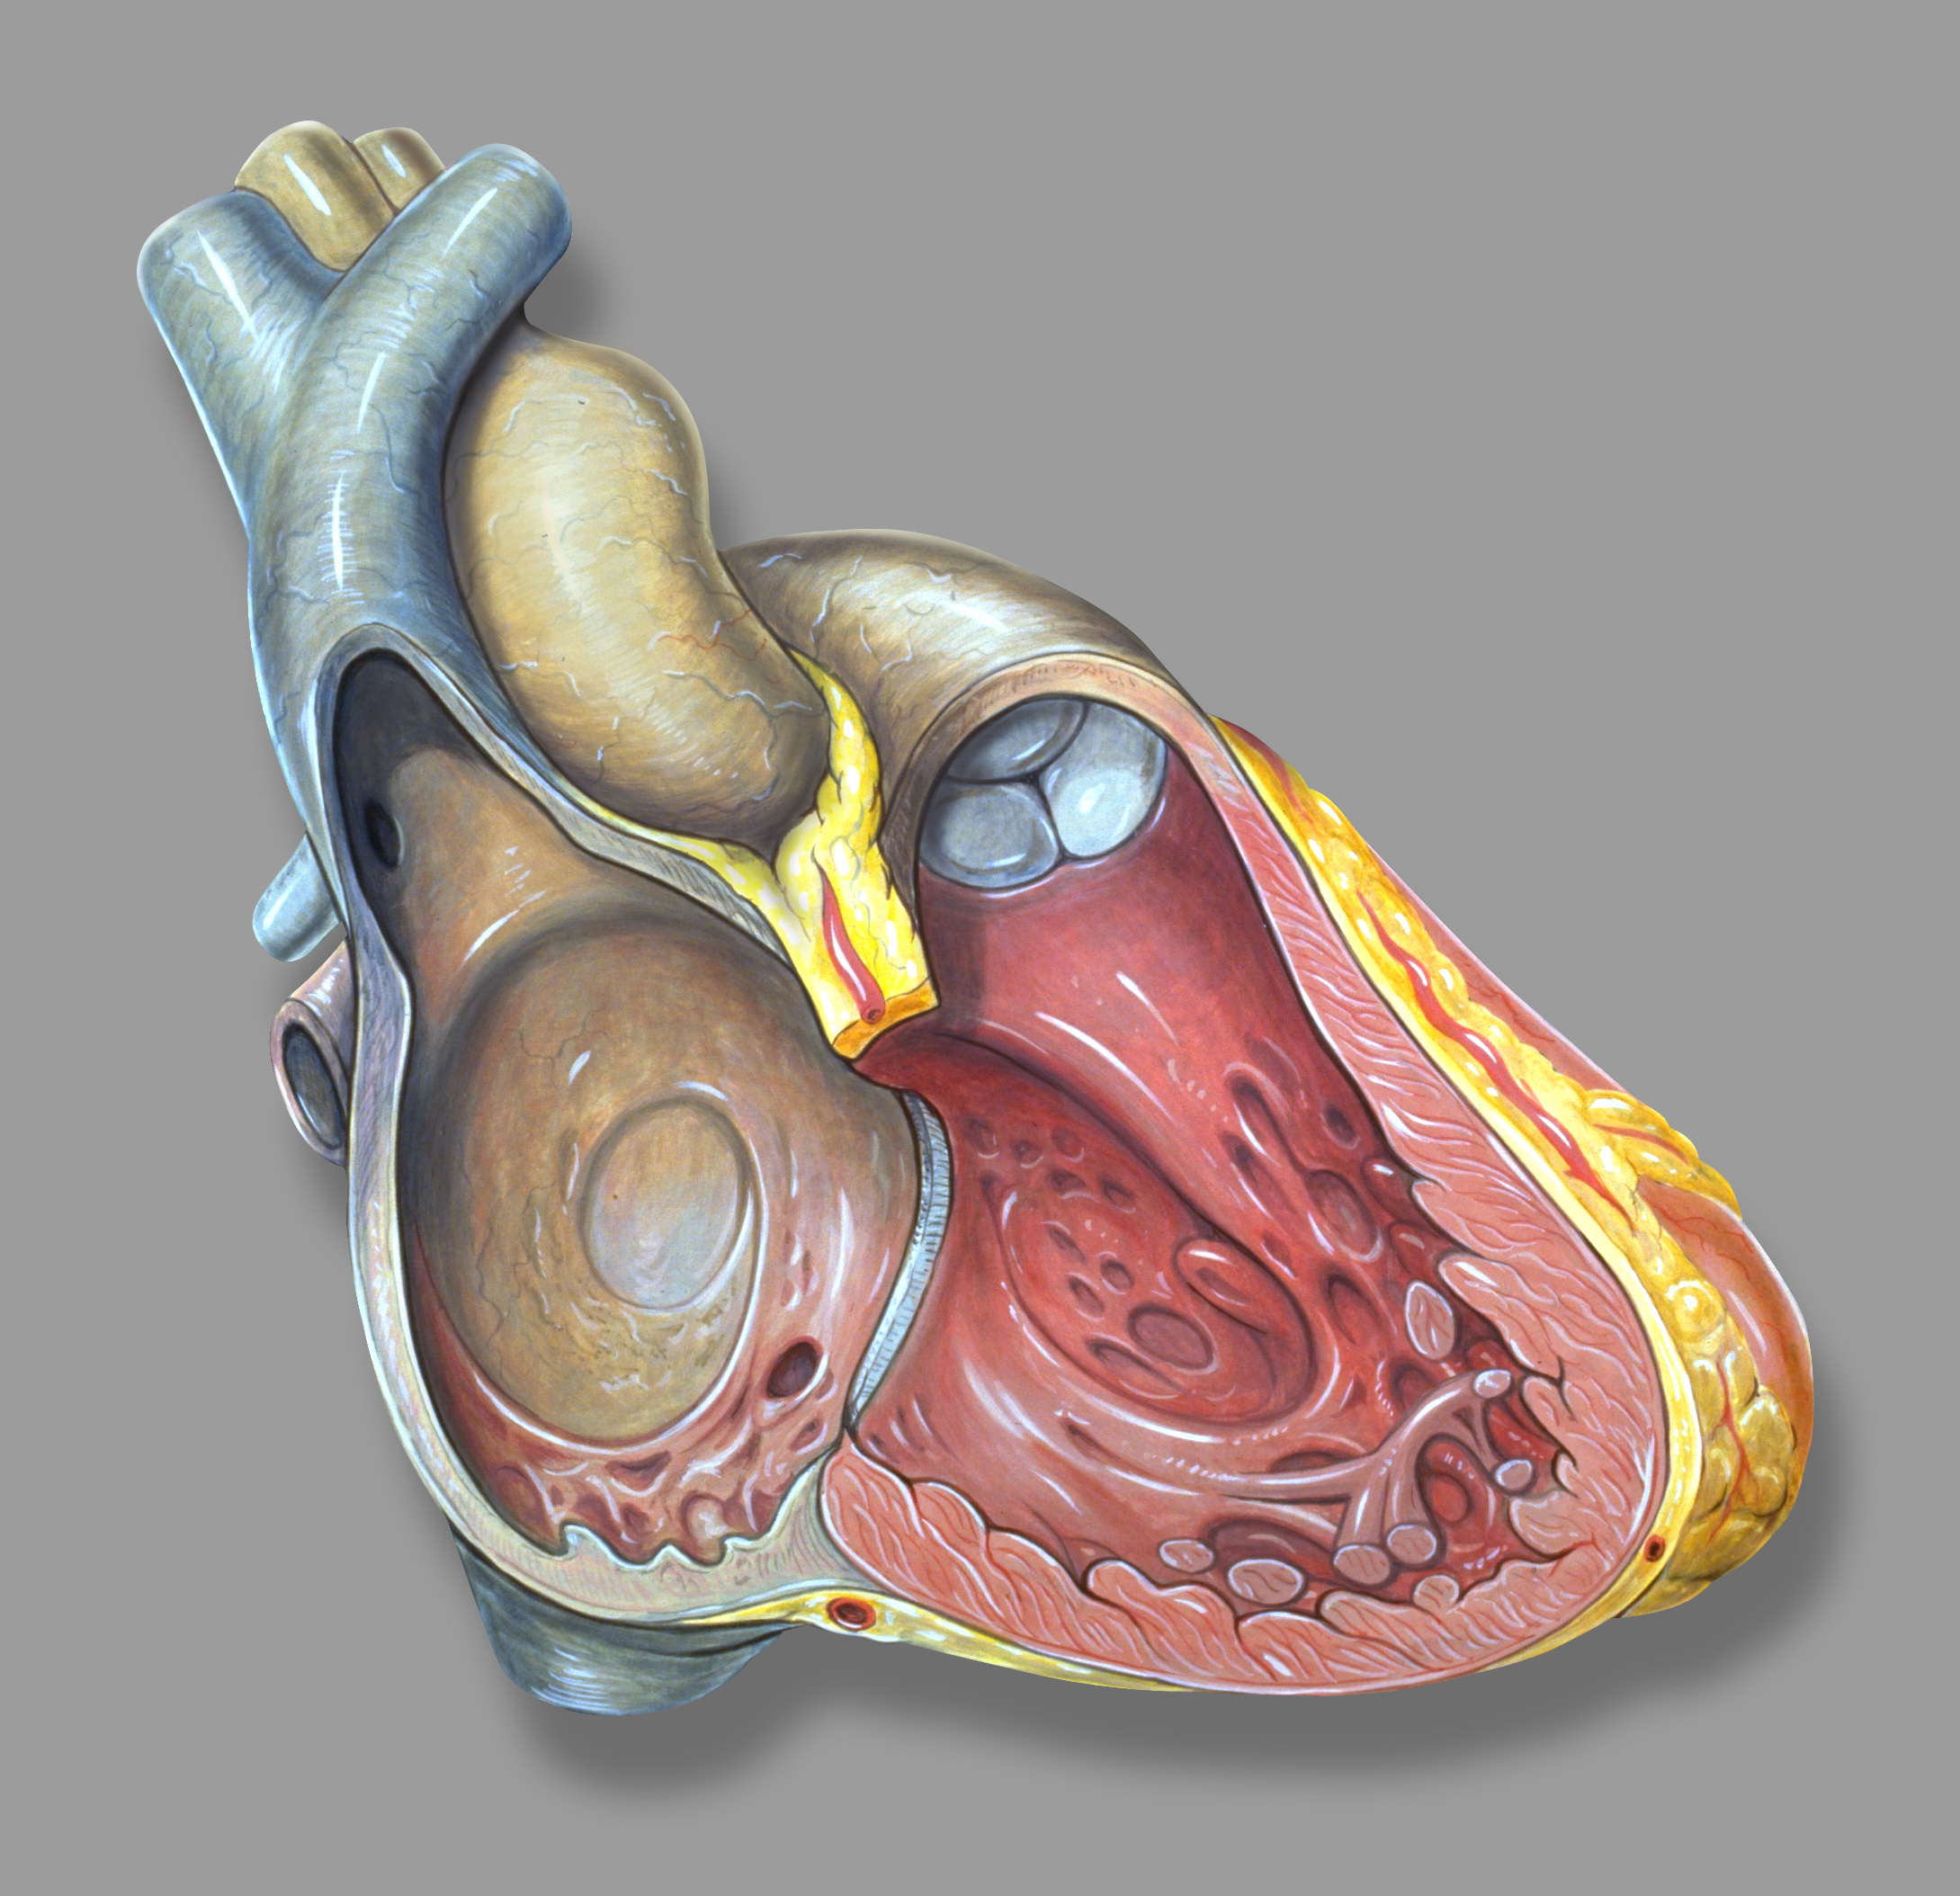

인간의 심장은 우심방, 좌심방, 우심실, 좌심실의 네 개의 방으로 구성되어 있다. 심방은 위쪽에 있는 두 개의 방으로, 혈액을 아래쪽 두 개의 심실로 보낸다.

우심방과 우심실을 합쳐 우심장이라 부르고, 좌심방과 좌심실을 합쳐 좌심장이라고 부른다. 심방에는 입구에 판막이 없기 때문에,[2] 정맥 박동이 정상적으로 나타나며, 경정맥에서 경정맥압으로 확인할 수 있다.[3][4]

내부에는 거친 빗살근과 히스의 결절능선이 있는데, 이는 심방 내부와 우심방의 매끄러운 부분인 ''정맥동''의 경계 역할을 한다. 정맥동은 대정맥과 관상정맥동의 개구부를 둘러싸고 있는 성인의 잔재이다.[5] 각 심방에는 심방 부속지가 붙어 있다.

2. 1. 우심방

우심방은 상대정맥, 하대정맥, 전심장정맥, 최소심장정맥, 관상정맥동에서 산소가 제거된 혈액을 받아 삼첨판을 통해 우심실로 보낸다. 우심실은 이를 다시 폐동맥으로 보내 폐순환을 하도록 한다.2. 1. 1. 우심방 부속지

'''우심방 부속지'''는 우심방의 앞쪽 윗부분에 위치하며, 앞에서 보면 쐐기 모양 또는 삼각형 모양으로 보인다. 기저부는 상대정맥을 둘러싸고 있다.[6] 우심방 부속지는 우심방의 주머니 모양 연장부이며 빗살근의 섬유망으로 덮여 있다. 심방 중격은 우심방과 좌심방을 분리하며, 이는 우심방의 함몰 부위인 난원와로 표시된다. 심방은 탈분극에 의해 칼슘이온이 관여한다.2. 2. 좌심방

좌심방은 좌우 폐정맥에서 산소화된 혈액을 받아 승모판 (좌심실판막)을 통해 좌심실로 보내 대동맥을 거쳐 전신 순환으로 펌프질한다.[7][8]2. 2. 1. 좌심방 부속지